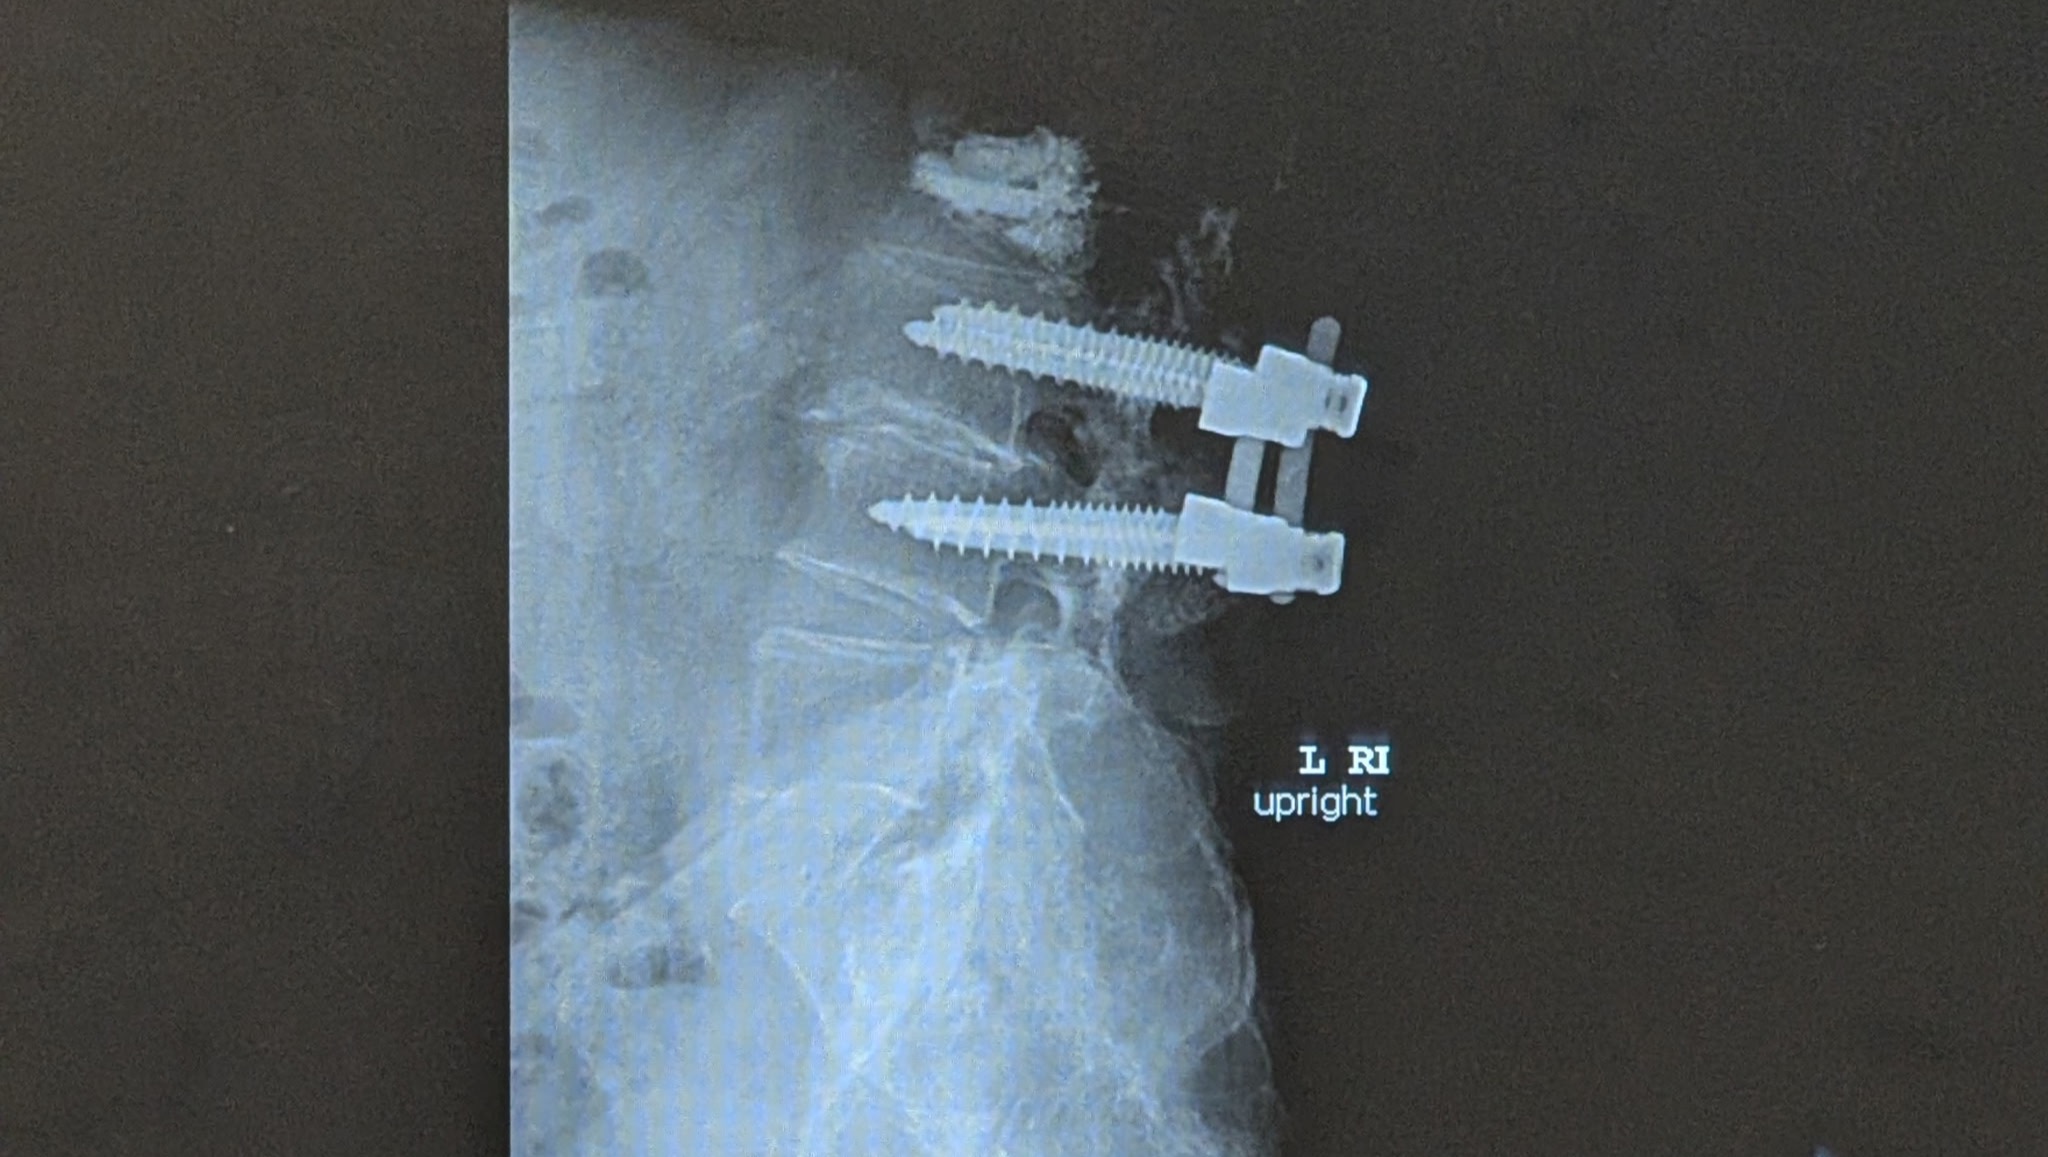

Now, back to the story. I kept after my doctor with little more than Aleve for pain, and finally, my wife and I went in and asked for an MRI to find out what was wrong. Long story short, I had two lower lumbar vertebrae that were constantly slipping in and out of position and an adjacent vertebra that had a compression fracture. I was referred by my primary doctor to the best neurosurgeon in Humboldt, Dr. Messegee. She did an amazing job alongside her amazing surgery team and incredible recovery team. I was in the hospital for 4 days. Current medical science is incredible.